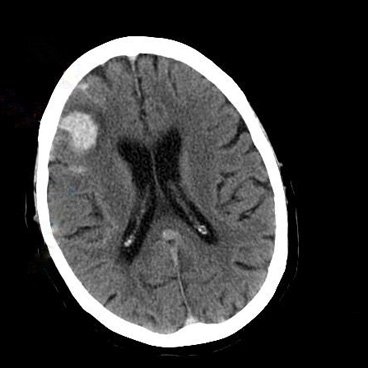

Brain tumors and head trauma, including concussions, can elevate pressure inside the skull, potentially crushing brain tissue or cutting off the brain’s blood supply. Monitoring pressure in the brains of such patients could help doctors determine the best treatment, but the procedure is so invasive — it requires drilling a hole through the skull — that it is done only in the most severely injured patients.

Pressure in the brain, also known as intracranial pressure (ICP), can rise due to the presence of excessive fluid (blood or cerebrospinal fluid), a brain tumor or swelling of the brain.